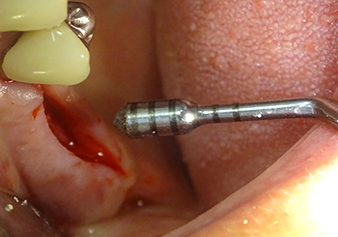

Following atraumatic preparation of the mucoperiosteal flap, the implant position was marked with the I1 instrument and the site prepared – until initial resistance was felt. Piezosurgical instruments were used in an up and down movement without any pressure being exerted. The piezoelectric vibration produced the desired and efficient cavitation.

The I2A instrument (diameter 2.0 mm) was then used to perforate the sinus floor intermittently and on the smallest scale possible. This special piezosurgical method ensures that the Schneiderian membrane is not damaged. When the Z25P was used, the membrane was already lifted slightly by the coolant supplied via the instrument tip (Fig. 3). The coolant quantity was just 50% in order to avoid high pressure in the implant bed.